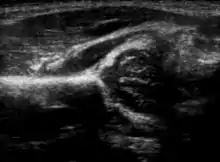

Imaging

Hip dysplasia can be diagnosed by ultrasound[42] and projectional radiography ("X-ray").[43] Ultrasound imaging is generally preferred at up to 4 months due to limited ossification of the femoral head up until then, and is the most accurate method for imaging of the hip during the first few months after birth. However, in most instances, ultrasound screening should not be performed before 3 to 4 weeks of age because of the normal physiologic laxity.[44][notes 1] When universal with targeted ultrasound screening was compared, the former results in an insignificant reduction in the late diagnosis of hip dysplasia, which is why universal ultrasonographic screening of newborn infants is not recommended by the American Academy of Pediatrics.[11]

Despite the widespread use of ultrasound, pelvis X-ray is still frequently used to diagnose or monitor hip dysplasia or for assessing other congenital conditions or bone tumors.[45]